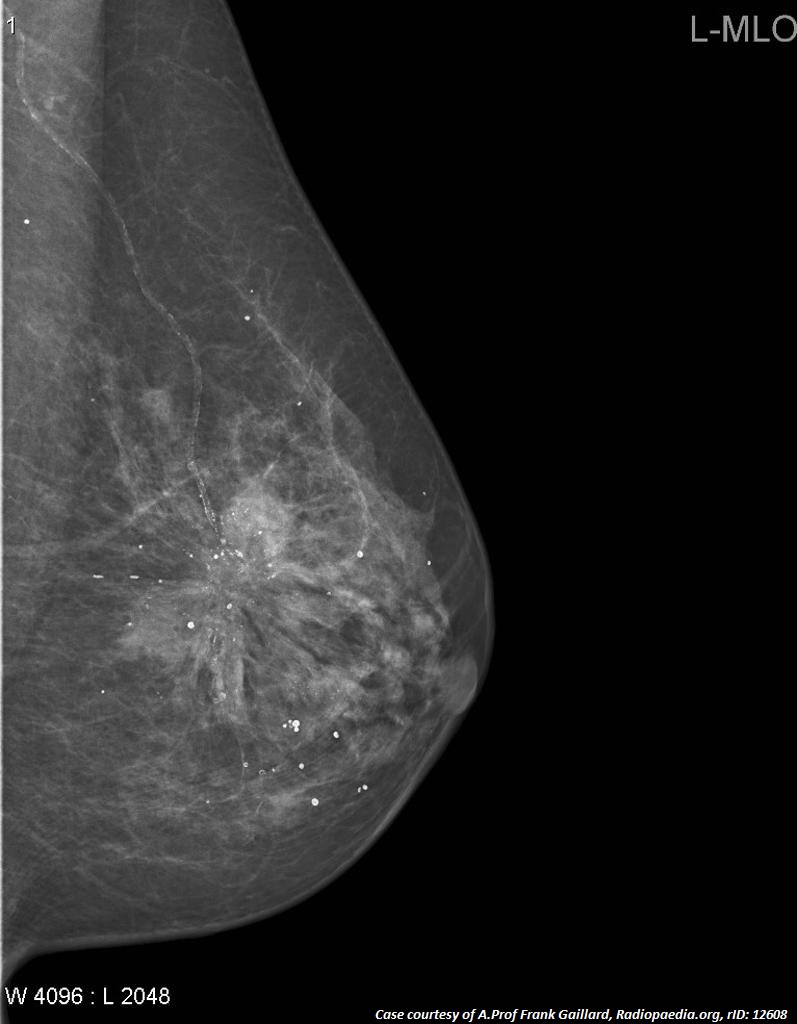

Diagnostic Imaging: Breast, 2nd Ed. ― Published by Amirsys。Breast Imaging 2 Fall 2025 | Canadian Association of Medical。Quantra® 2.2 | Breast Density Assessment Software | Hologic。マンモグラフィーや超音波などの診断技術を網羅した、拡大改訂版の医学書。Computer-aided detection enhances breast MRI | AuntMinnie。- 書籍名: Diagnostic Breast Imaging- 著者: Sylvia H. Hewayng-Köbrunner, D. David Dershaw, Ingrid Scherer- 版: 第2版, 拡大改訂版- 出版社: Thieme- 内容: マンモグラフィー、超音波、磁気共鳴画像、介入手技に関する情報ご覧いただきありがとうございます。。